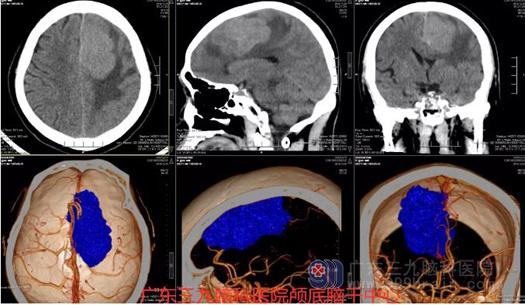

图1:术前CTA示左侧额部镰旁巨大占位性病变,其内示多发细小血管影,邻近双侧大脑前动脉受压右偏;右侧大脑后动脉主要由后交通动脉发出;双侧大脑前、中与后动脉、所示双侧颈内动脉与椎动脉及基底动脉走行稍僵硬、迂曲,部分管腔稍粗细不均,管壁未见粥样硬化斑块或钙化斑,未见闭塞、畸形血管或局限性囊状增粗影。